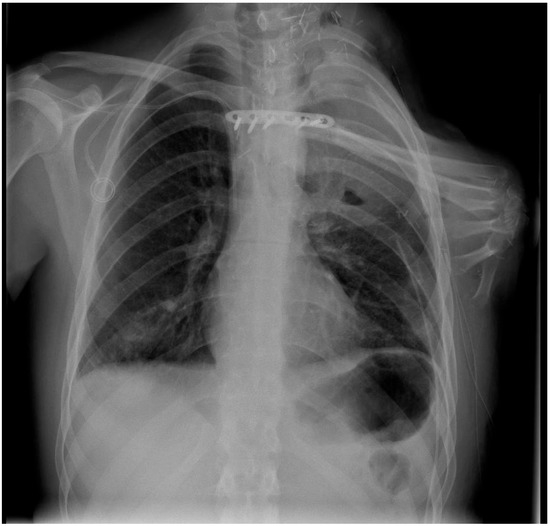

| 25 year old male with central chondroblastic osteosarcoma (cT2 cN0, cM1), extended FQA, including resection of the clavicle and the first three ribs | Brachial artery to thoracoacromial artery and cephalic vein to subclavian vein | Plate osteosynthesis between radius and sternum, 90° flexed wrist and fixation sutures between metacarpals and the lateral thoracic wall | Nerve coaptation between superior trunk and median nerve, middle trunk and radial nerve, and inferior trunk and ulnar nerve | Discharged after 11 days, stable osseous framework, Exitus letalis three months after surgery due to disseminated, primarily pulmonal, metastases |